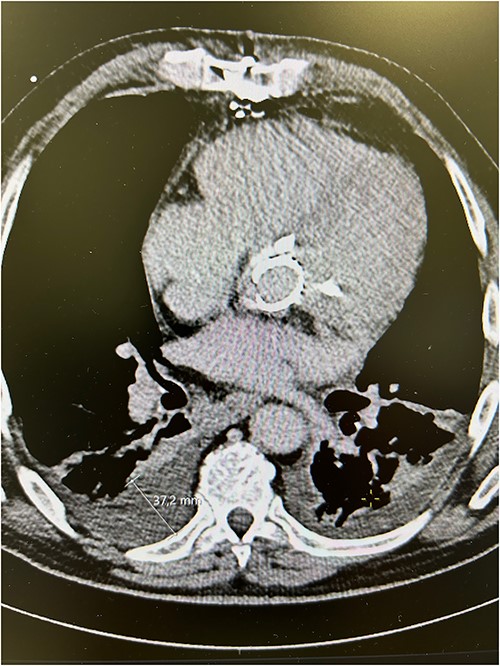

The patient experienced significant dyspnea, increased passiveness, decreased performance, and cardiac echocardiography revealed a destroyed, regurgitant, and stenotic aortic valve prosthesis with myocardial calcification of the left outflow track (Fig. 1) including a peak mean aortic gradient of 76/49 mmHg, Vmax 4.3 m/s and AVA 1.0 cm2 and significant regurgitation (Fig. 2). Minimal mitral valve regurgitation and some coronary artery stenosis were also present.

Preoperative computed tomography scans showing calcified aortic valve bioprosthesis in the aortic prosthesis together with pleural effusions.